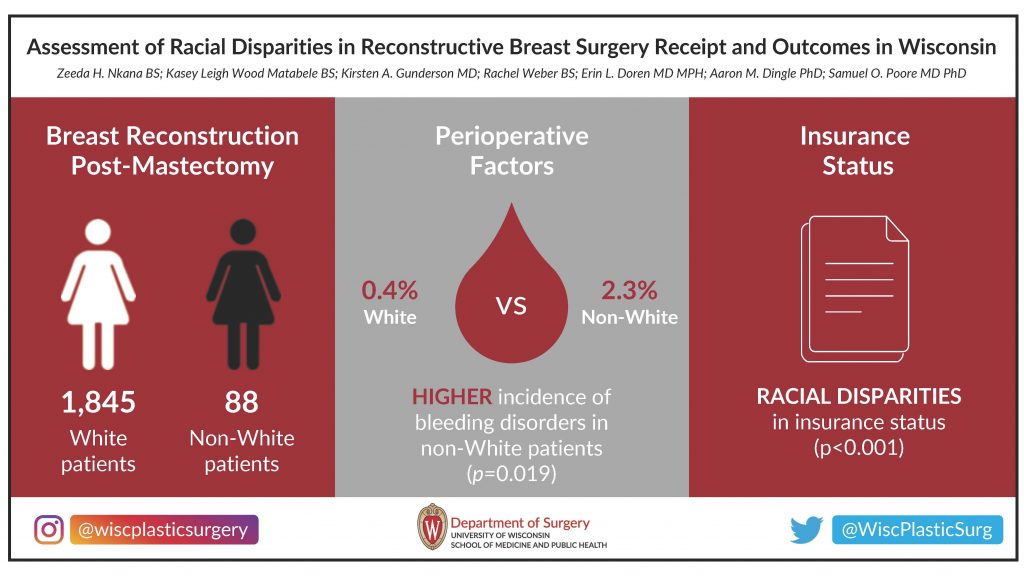

We also hold friendly competitions for the Best Surgery Science Image and the Best Visual Abstract, voted on by department members during the summit. Get a glimpse of the finalists and winners below. And for a complete overview, check out the 2023 Research Summit Program Book.

Best Visual Abstract

First Place:

Runner Up:

Runner Up: